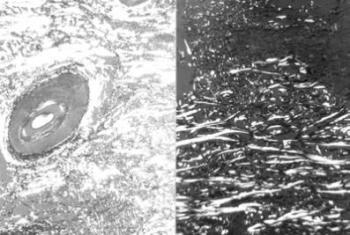

11. ábra. Bőrben lévő ideg (nervus facialis ág) velőshüvelyű idegrostjai. Római kori múmia bőre. Luxol Fast Blue festés, 200× nagyítás

12. ábra. A 19. századi férfi múmia aortájában kifekélyesedett atheromás plakk, a koleszterin kristályok helyét tű alakú üregek (csillag) jelzik. HE festés 150× nagyítás

13. ábra. A veseartéria falában kitűnően feltüntethető az elasztikus membrán. 19 éves nő (meghalt 1801) veséje. Elastica-van-Gieson festés, 150× nagyítás